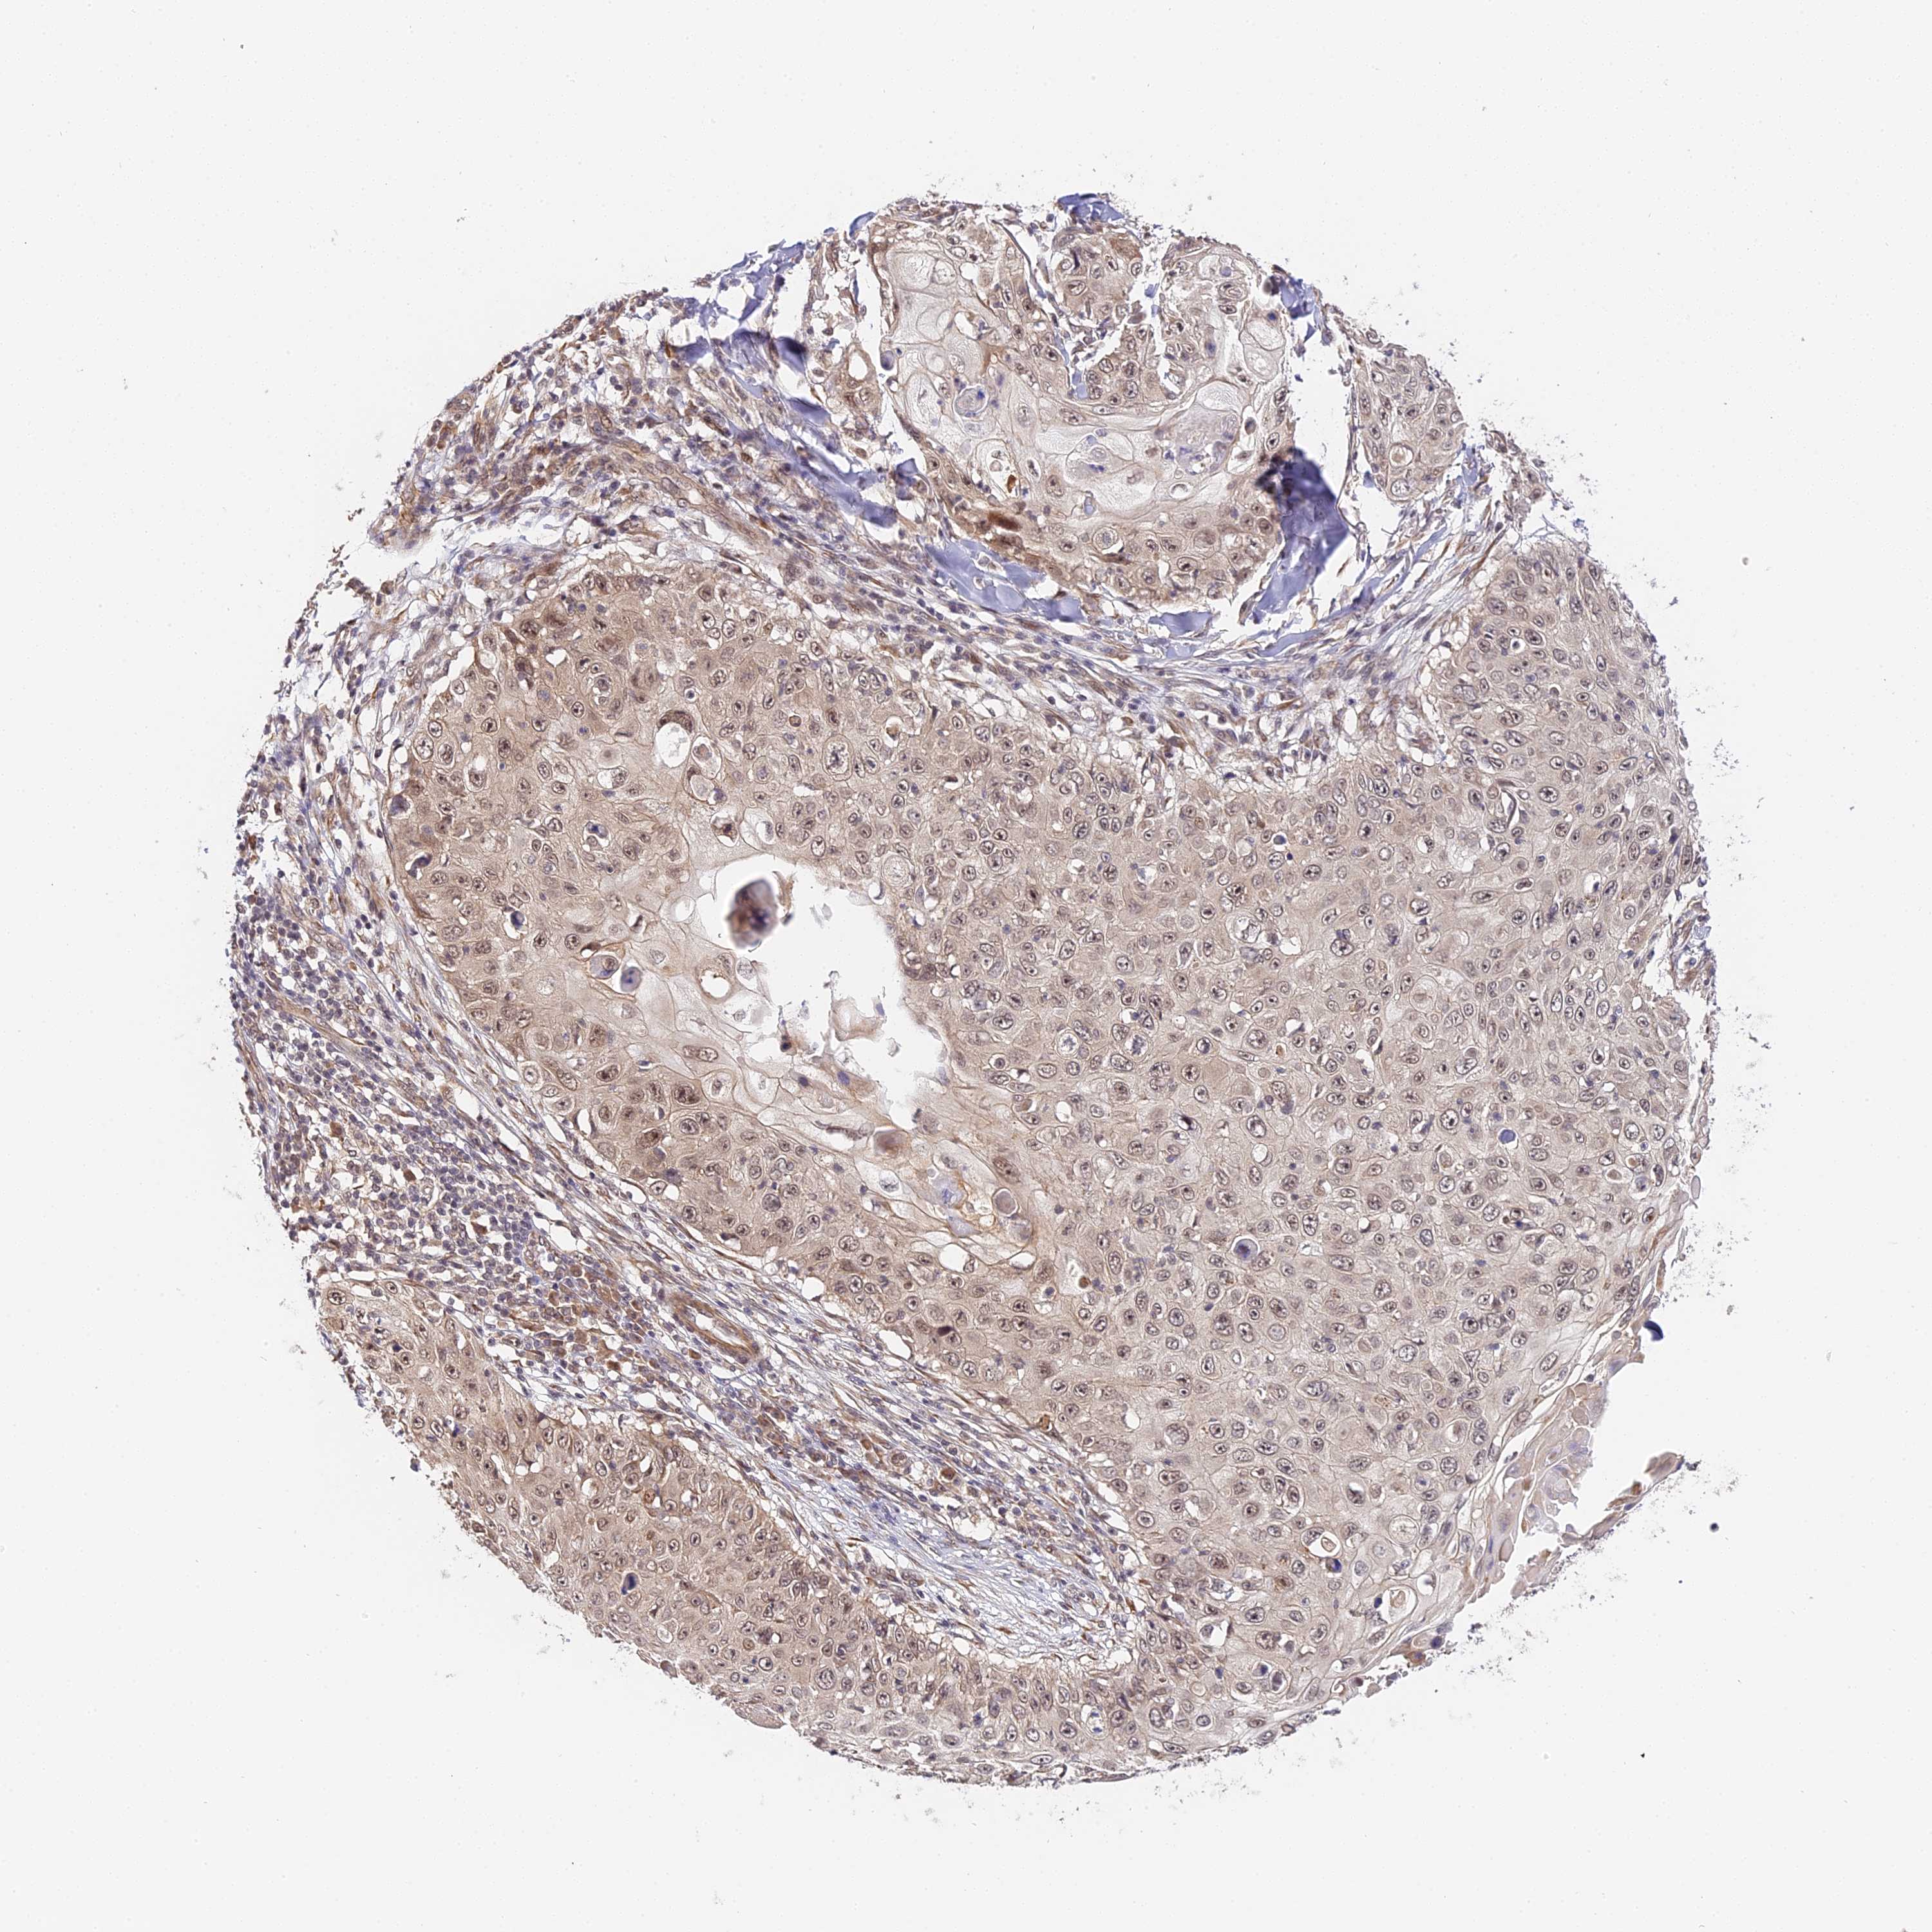

SKIN CANCER - Protein expressioni

A mouse-over function shows sample information and annotation data. Click on an image to view it in a full screen mode. Samples can be filtered based on level of antibody staining by selecting one or several of the following categories: high, medium, low and not detected. The assay and annotation is described here.

Antibody stainingi

Antibody staining in the annotated cell types in the current human tissue is reported as not detected, low, medium, or high, based on conventional immunohistochemistry profiling in selected tissues. This score is based on the combination of the staining intensity and fraction of stained cells.

Each image is clickable and will lead to virtual microscopy that enables deeper exploration of all samples and also displays staining intensity scores, fraction scores and subcellular localization as well as patient and tissue information for each sample.

Antibody HPA041045

Antibody HPA041968

Staining

High

Medium

Low

Not detected

Squamous cell carcinoma, NOS

Basal cell carcinoma